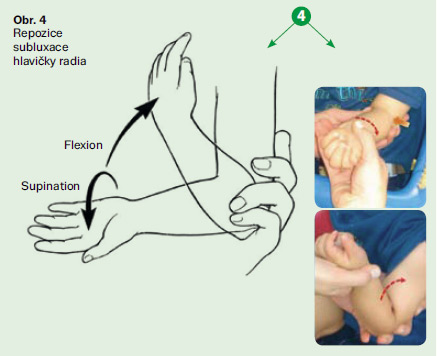

Pronatio dolorosa (lat. bolestivá pronace, Chassaignacova obrna) je bolestivé držení lokte u malých dětí, vzniklé po prudkém tahu a rotaci ruky, při kterém dochází k subluxaci hlavičky radia v lokti s uskřinutím lig. anulare. Nejčastěji vzniká u dětí mezi 2. a 4. rokem při tahu za zápěstí či předloktí např. vytahováním dítěte za jednu horní končetinu vzhůru, zejm. při zabránění pádu. Patří k nejčastějším úrazům malých dětí.

Pronatio dolorosa je méně závažné, ale časté poranění, které vzniká při násilném tahu za pronované a hyperextendované předloktí, kdy ligamentum anulare radii (vřetenní prstencový vaz) sklouzne přes hlavičku radia a uskřine se mezi hlavičku radia a capitulum humeri (do radiohumerálního kloubu). Vzniká nejčastěji tak, že dítě vedené za ruku padá a rodič ve snaze zabránit pádu ho prudce zatáhne za ruku. Tělo dítěte rotuje kolem ruky a působí celou vahou na loketní kloub. Dále může vzniknout při manipulaci s nespolupracujícím dítětem či při hře, kdy starší kamarád nebo člen rodiny točí (pohupuje) dítětem za jeho ruce či předloktí.

Nejčastější příčinou subluxace hlavičky radia je zatáhnutí dítěte za ruku. Ke způsobení úrazu není potřeba velké síly.

- Chytíte dítě za ruku, abyste zabránili jeho pádu

- Zvednete dítě do výšky za jeho ruce nebo předloktí

- Zatáhnete dítě za ruku při oblékání rukávů

- Budete pohupovat dítě za ruce

- Škubnete za ruku dítěte, aby šlo rychleji nebo opačným směrem

- Zvednete dítě za jednu ruku např. přes nějakou překážku